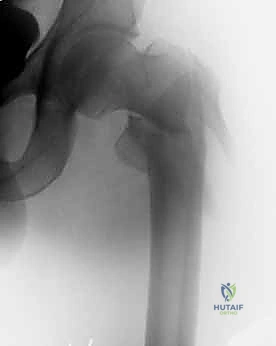

التصوير الطبي المتقدم

- الأشعة السينية (X-rays): هي المعيار الذهبي الأولي. يتم أخذ صور من الأمام للخلف (AP) وصور جانبية (Lateral) للحوض والورك المصاب. تكشف هذه الصور عن موقع الكسر، نوعه (بسيط أم مفتت)، ودرجة الإزاحة.

مجموعة من الصور الإضافية التي توضح مراحل دقيقة من العمل الجراحي المعقد الذي يجريه الأستاذ الدكتور محمد هطيف لضمان أعلى درجات الدقة الميكانيكية الحيوية: